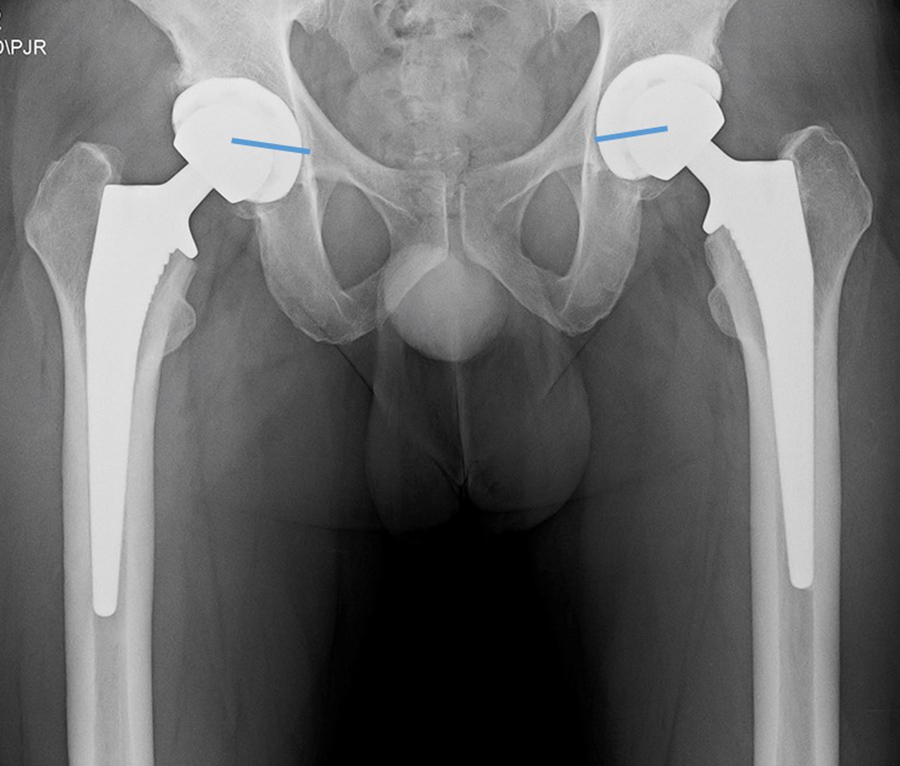

Bilateral total hip arthroplasty (THA) |

38 year old man with bilateral THA for advanced osteoarthritis. |

| Bilateral total hip arthroplasty (THA) |

| 38 year old man with bilateral THA for advanced osteoarthritis. The acetabular cup on an AP view of the pelvis should have 30-50 degrees of lateral inclination, which is measured as the angle between the rim of the acetabular cup and a line tangential to the ischial tuberosities. |

38 year old man with bilateral THA for advanced osteoarthritis. On a true cross-table lateral view of the hip there is normally 5-25 degrees of anteversion which is measured as the angle between the rim of the acetabular cup and a line drawn perpendicular to the horizontal surface. |

38 year old man with bilateral THA for advanced osteoarthritis. The distances from a line (C) between the centers of the femoral heads to a line running tangential to the ischial tuberosities (A) should be equal on each side, and the distances between the centers of the femoral heads to a line (B) running tangential to the tops of the greater trochanters should be equal on each side. Lines A, B, C should be parallel. |

38 year old man with bilateral THA for advanced osteoarthritis. The distances from the centers of the femoral heads on each side to the tops of the acetabular tear drops should be equal. |